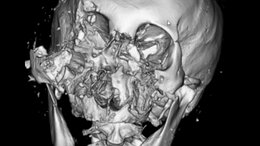

クマ外傷の9割は“顔面”を損傷「鼻を拾って外科手術で…」100例以上診た医師が語るクマ襲撃のリアル「精神的なダメージも深く」後遺症でかすむ日常